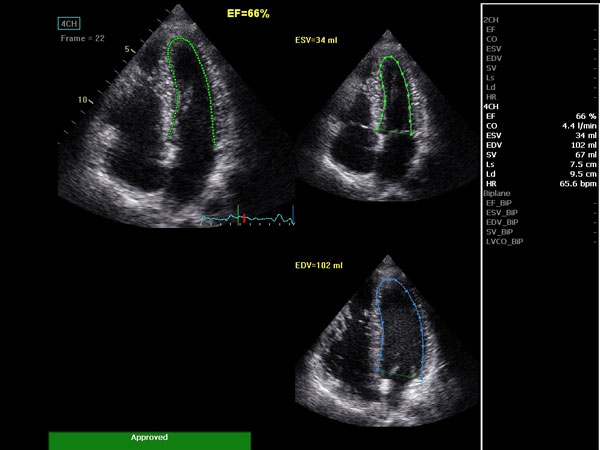

Ключевым сегментом диагностической медицины, где функционал данного устройства раскроется в полной мере, является кардиология. Благодаря высокочастотным датчикам и превосходным изображениям, можно рассмотреть без лишнего шума детали сердца пациента и поставить точный эффективный диагноз.

Мощные возможности для современной кардиологии от Vivid T8

• TVI (Tissue Velocity Imaging) — цветовой тканевой доплер — отображение динамических данных от подвижных тканей сердца; дает возможность без труда определить функцию левого желудочка.

• AutoEF (Auto Ejection Fraction) — функция автоматической недоплеровской количественной оценки глобальной сократительной функции левого желудочка с выделением зоны интереса по технологии спекл-трекинга.

• AFI (Automated Function Imaging) — автоматическое отображение функции ЛЖ — функция позволяет производить качественную и количественную недоплеровскую оценку региональной сократительной функции левого желудочка.